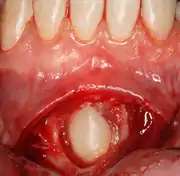

Pericoronitis

Pericoronitis is an infection of the soft tissue that covers the crown of an impacted tooth and is usually caused by the normal oral microbiota. For most people there exists a balance between the host defenses and the oral micriobiota but if the host defenses are compromised like during minor illness such as influenza or an upper respiratory tract infection, pericoronitis results. Another common cause is entrapment of food beneath the gum flap (also called an operculum). Pericoronitis can present as a mild infection or severe infection. In its mildest form it is just a localized tissue swelling and soreness whereas in severe forms the swelling is slightly larger even sometimes creating trismus (difficulty opening the mouth).

Sometimes, a surgeon may wish to expose the canine for aesthetic purposes. This may be achieved through open or closed exposure. Studies show no advantage of one method over another.[11] A laser can be used to uncover superficially impacted teeth with no bleeding and quick recovery [12][13][14]